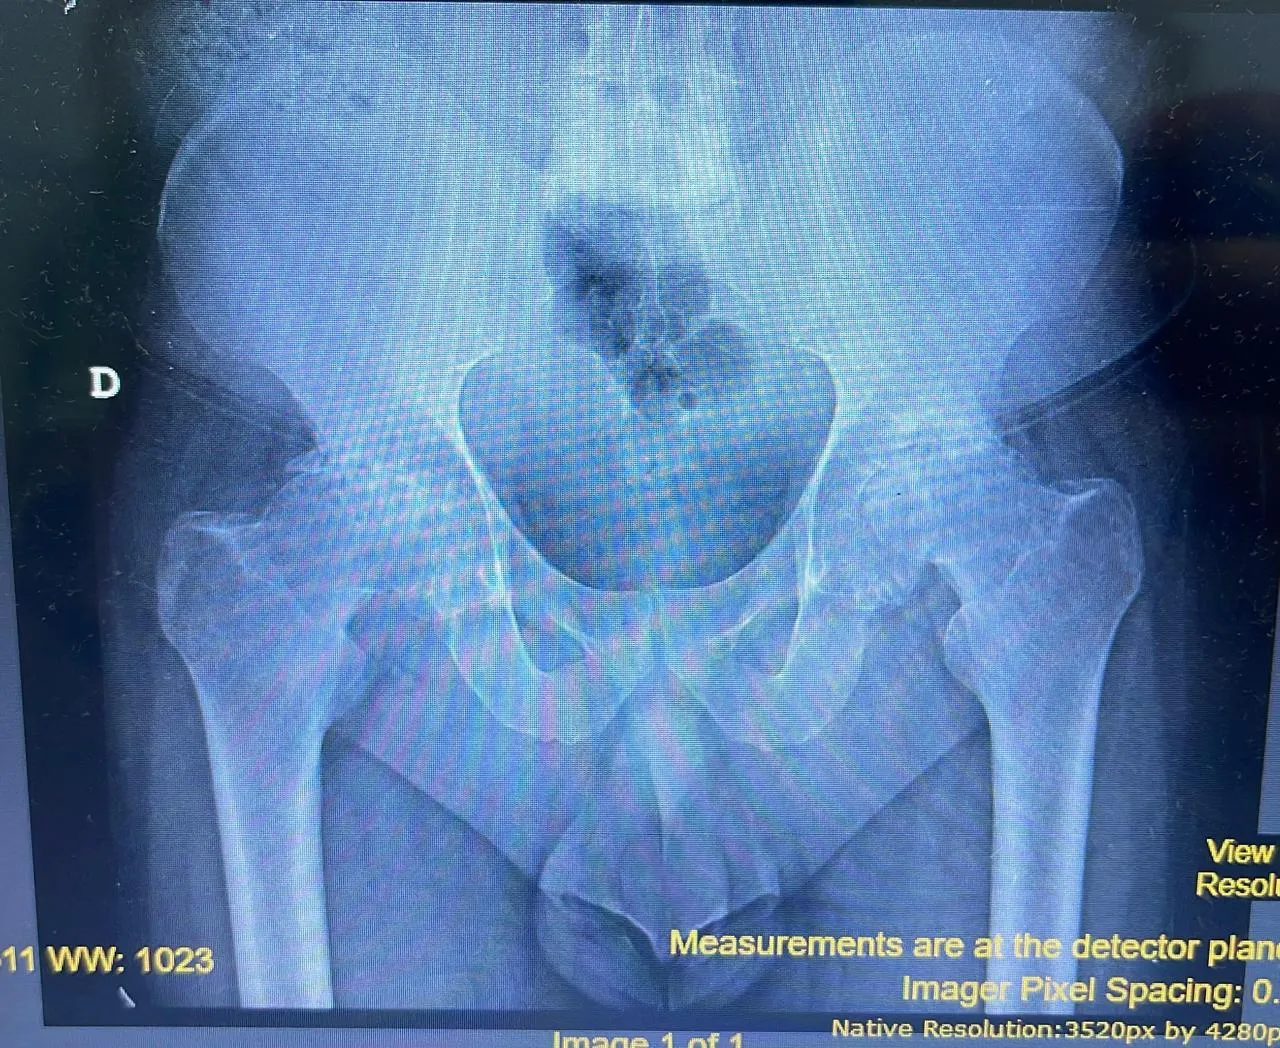

Radiografía digital preoperatoria de pelvis con mediciones para planificación quirúrgica

Radiografía digital preoperatoria para planificación quirúrgica del reemplazo bilateral.